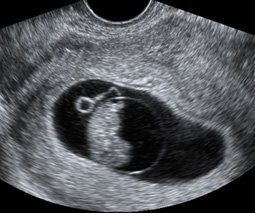

Early Pregnancy Scan

Early pregnancy scan is recommended if you have a history of Miscar​riage or ectopic pregnancy or if there is bleeding or lower abdominal pain

It is indicated when last menstrual period date is uncertain or for suspected multiple gestation to allow for reliable determination of chorionicity or amnionicity. First trimester ultrasound is also recommended for suspected ectopic pregnancy, molar pregnancy, and suspected pelvic masses. First trimester ultrasound is also recommended for early assessment of anatomic development in situations of increased risk for major fetal congenital malformations.

The aims of this scan are to determine the number of embryos present and whether the pregnancy is progressing normally inside the uterus.

• Confirmation of an early/viable pregnancy

• Measurement of the gestation sac and the Crown Rump Length (CRL)(if possible)

• Detection of heartbeat. (If Pregnancy is more than 6 Weeks.

• Between 6 and 10 weeks.